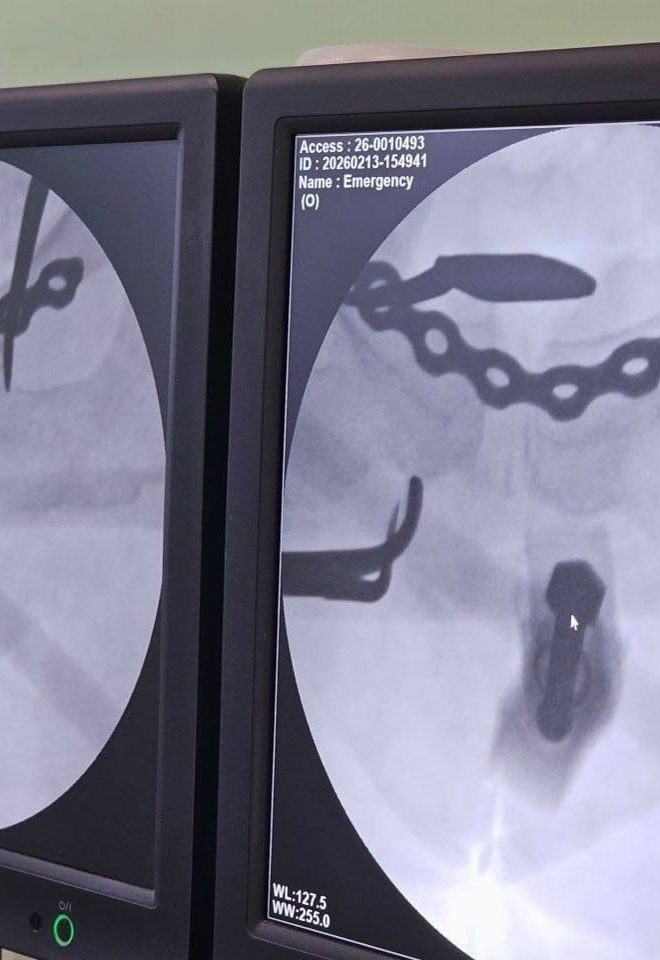

Медики диагностировали крайне тяжелые повреждения таза: двусторонний перелом боковых масс крестца и разрыв лонного сочленения.

Лечение проводилось с применением аппарата внешней фиксации переломов, который позволяет быстро и малоинвазивно стабилизировать состояние пациента.

1⃣ На первом этапе, сразу после поступления, дежурная бригада в рамках противошоковых мероприятий выполнила закрытую репозицию костей таза и их фиксацию внешним аппаратом.

Операция заняла около 20 минут и была выполнена всего через два прокола кожи, что позволило стабилизировать состояние пациентки. Вскоре женщину перевели из реанимации в профильное отделение.

2⃣ На втором этапе врачи зафиксировали переломы: крестец укрепили канюлированными винтами через минимальные проколы, а разрыв лонного сочленения — титановой пластиной через мини-доступ.